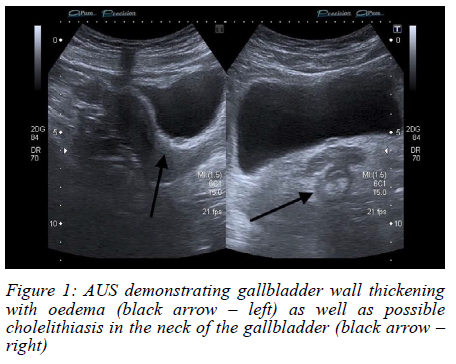

An abdominal ultrasound (AUS) showed a possible stone in the gallbladder neck, with a thickened and oedematous gallbladder wall (Figure 1). No masses were noted on sonar. The history of loss of weight was further investigated. A colonoscopy was performed, which was normal. A computed tomography (CT) scan did not show any concerning features, and a thickened gallbladder wall was once again visualised (Figure 2, 3).

Radiologically, CT and ultrasound findings are nonspecific, ranging from wall thickening to mass-like lesions with necrosis or calcification.68 These features overlap significantly with gallbladder malignancy or chronic inflammation,6,8 making preoperative diagnosis challenging. Radiologic "red flags" suggesting TB over carcinoma include gallbladder wall with necrotic core, multiple flecked calcifications, broad-based micronodular lesions, pericholecystic oedema, and necrotic lymph nodes.6 Consequently, in the absence of systemic TB features or pulmonary symptoms, most diagnoses hinge on postoperative histopathology, where necrotising granulomas with or without acid-fast bacilli confirm the diagnosis.9